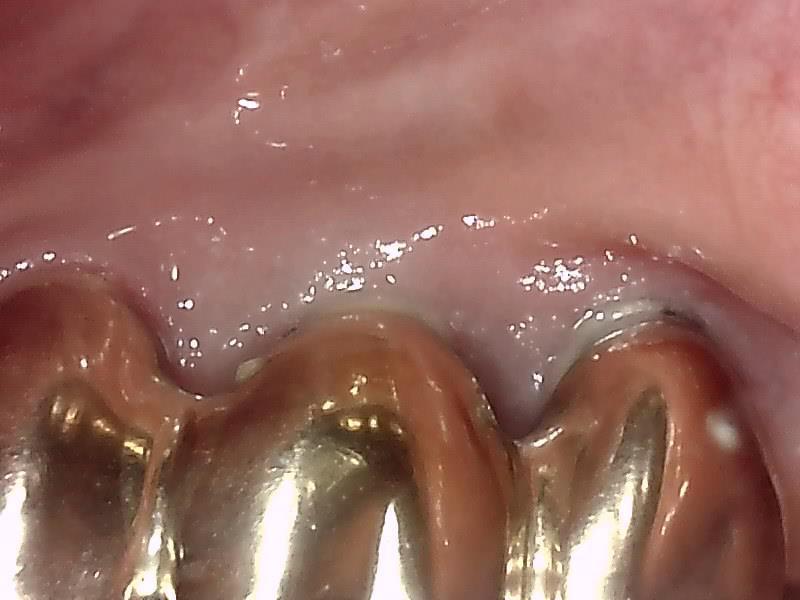

本症例はインプラントを消毒しても治らなかったので、インプラントのバイ菌を除去する手術で

なおさせていただき、歯ぐきはしっかりと引き締まりました。